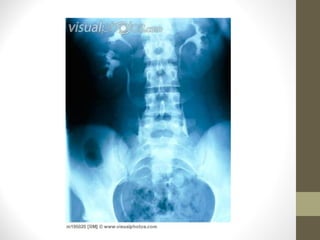

• At which positions do stones cause problems?

•

Infundibulum

PUJ

Pelvic Brim

Over Iliac Vessels

VUJ